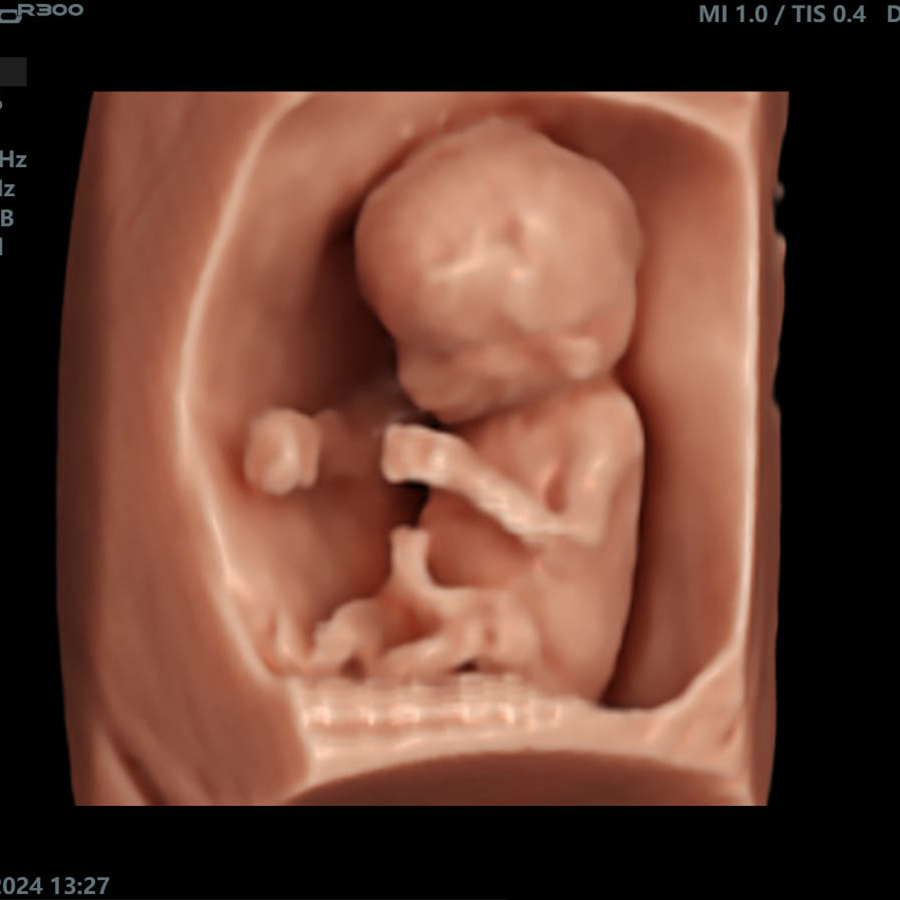

Ginecología

- Smart Face

- Smart 3D/4D

- Impresión 3D

- MCUT

- Free View

- VAim OB